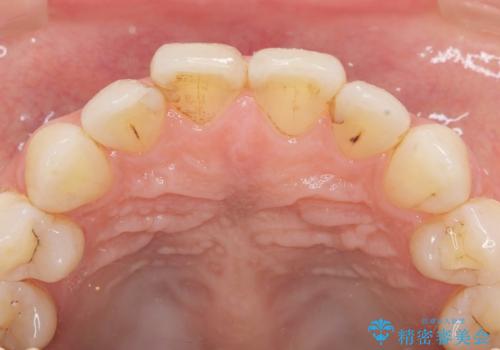

- 数年前に前歯の虫歯治療し、コンポジットレジン修復がなされてい箇所の審美障害の改善を希望され来院されました。

再度レジン修復を行うか、劣化のスピードは遅いが歯の削合が必要なセラミッククラウンの治療の選択肢をご提案し、今後のやりかえの心配の少ないセラミッククラウン治療を希望されました。